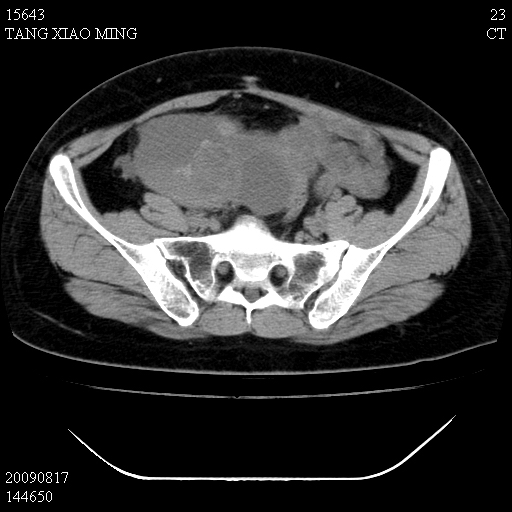

标题: CT21692:盆腔病变

女,33岁,右下腹痛2年余,既往宫外孕病史,如在我院手术,结果下周公布,

可能的诊断。1子宫内膜异位【子宫腺肌症并右卵巢巧克力囊肿】;2 右卵巢囊腺瘤。子宫肌瘤

1)考虑卵巢巧克力囊肿,不排除卵巢囊腺瘤。2)子宫肌瘤可能。

卵巢囊腺瘤,子宫肌瘤,直肠壁厚,不除外占位.